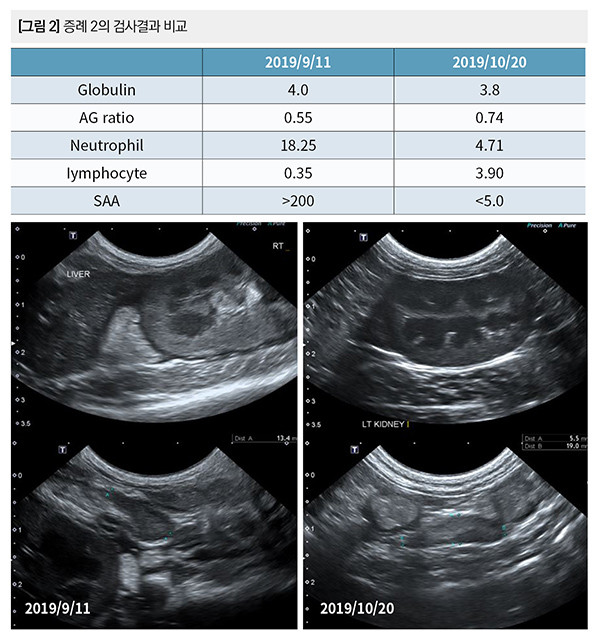

혈구검사에서 백혈구 증가증(18,250개/ul)과 림프구 감소증(350개/ul), 경미한 빈혈(HCT 22.8%)을 보였다. 글로블린이 4.0g/dl로 경미하게 상승했고, AG ratio는 0.55로 감소했다. SAA가 200 ug/ml 이상으로 상승했다. 초음파상에서 경미한 복수와 복강내 림프절의 종대가 관찰되었다.

추가적인 검사는 실시할 수 없어서 FIP로 잠정 진단하고, GS-441524 또는 GC376을 투여할 것을 추천했다. 1개월 후 재검에서 초음파상 복수는 개선 되었지만 림프절의 종대는 관찰되었다.

호중구와 림프구의 수치가 정상으로 회복했고, SAA도 5 ug/ml 미만으로 감소했다. AG ratio는 0.55에서 0.74로 상승했다. 이후 추적검사는 실시하지 못했지만, 1개월 이내에 개선되는 것을 확인했다.